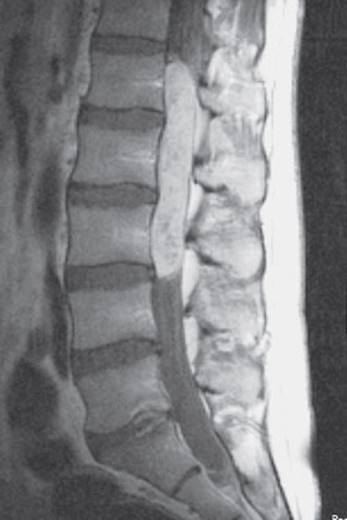

Diagnostic evaluation. Nowadays, the definitive diagnostic study is MRI, though radiculography and myelographic CT are still sometimes needed (Fig. 12.9).

Fig. 12.9 Lumbar disk herniation in a 70-year-old man with neurogenic intermittent claudication due to degenerative lumbar spinal canal stenosis. The MRI (a) and myelogram (b) reveal compression of the dural sac and the nerve roots at the L2–3 (arrow) and L3–4 disk levels, as well as at L4–5 (less severe).